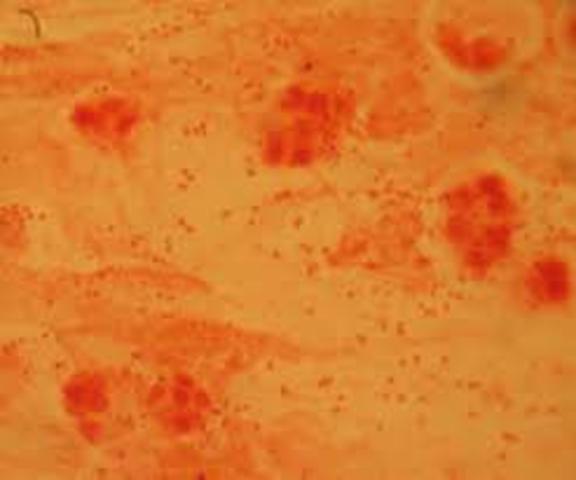

Bassi, asocia por primera vez la presencia de un hongo a una enfermedad (malagseno) presente en gusanos de seda

Eichstedt, identifico por primera vez a un microorganismo como el agente etiotogico de una enfermedad cutanea humana ( pititriasis versicolor)